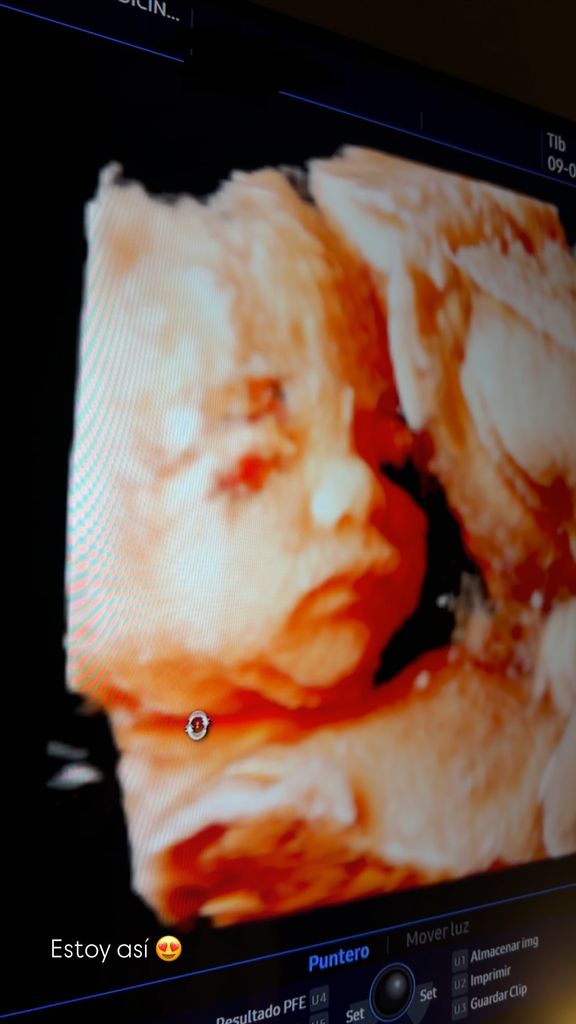

Sin embargo, el momento más especial llegaba con la ecografía en 4D de su bebé, que compartió con sus seguidores y en la que se aprecia con nitidez el rostro de la pequeña. Marta acompañaba la imagen con un “Estoy así” y un emoji de carita con corazones, un gesto que refleja la ilusión con la que espera a su hija, cuyo nacimiento está previsto para primavera. Como suele ocurrir en estos casos, la imagen ha despertado las primeras comparaciones sobre a quién se parecerá, si a Rodri o a Marta. Las opiniones están divididas, así que habrá que esperar a su llegada para descubrirlo.